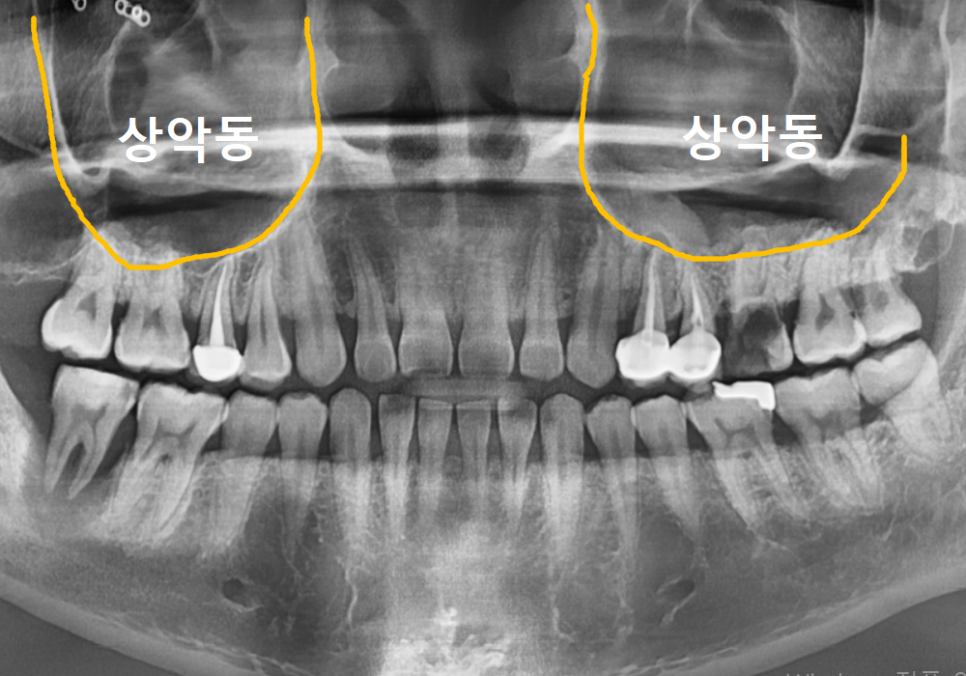

위쪽(#26): 상악동 거상술

위턱뼈 안쪽에는 '상악동'이라는

텅 빈 공기 주머니가 있습니다.

임플란트를 튼튼하게 심으려면

최소 7~8mm의 뼈 높이가 필요한데,

환자분은 뼈가 녹아

5.7mm밖에 남지 않으셨어요.

이런 경우 얇은 상악동 막을

조심스럽게 들어 올린 뒤

부족한 높이만큼 뼈를 채워주는

'상악동 거상술'이 필요합니다.